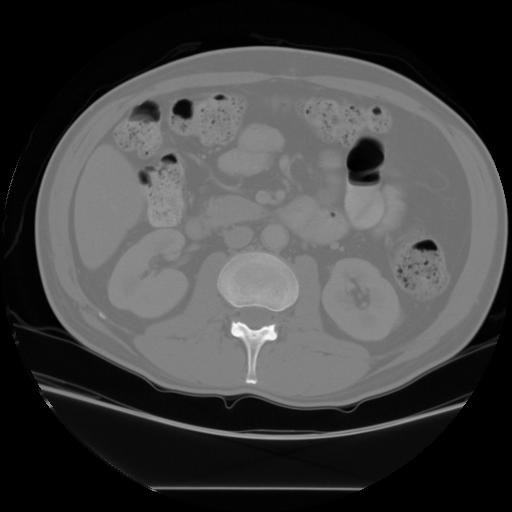

The main goal of this assignment is to find organs of interest in CT images, using techniques of binary vision in Matlab. The organs of interest are the kidneys, the liver, and the spleen, as shown below.